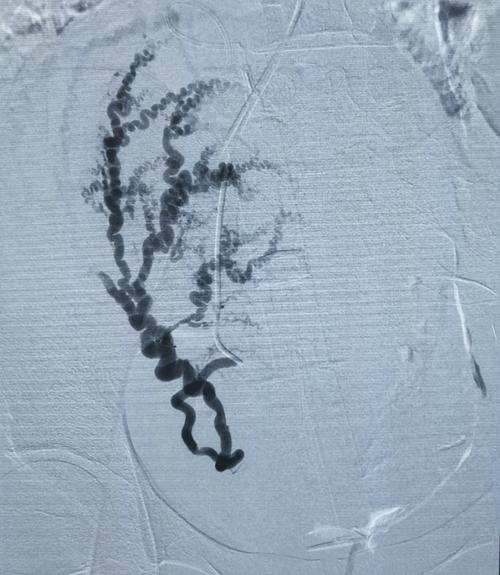

输卵管导丝介入后多久可以怀孕